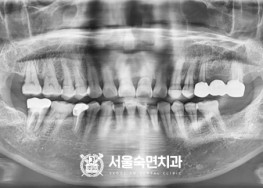

임플란트-치료-전후사진